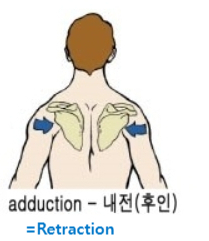

내전(후인, Adduction) / 외전(전인, Abduction) = Medial/lateral sliding around the curvature of the thorax

앞서 말했던 원인들에 의해서 겹갑골은 과도한 견갑골의 앞으로 빠진상태인 전인상태(견갑골 벌어짐, Protraction, 후인이 잘 안됨)와 견봉 올림(Acromial elevation)이 어려움에 의해서 충돌이 더욱 쉽게 일아날 수 있습니다.

1. 견갑골의 후인(Retraction) 회복